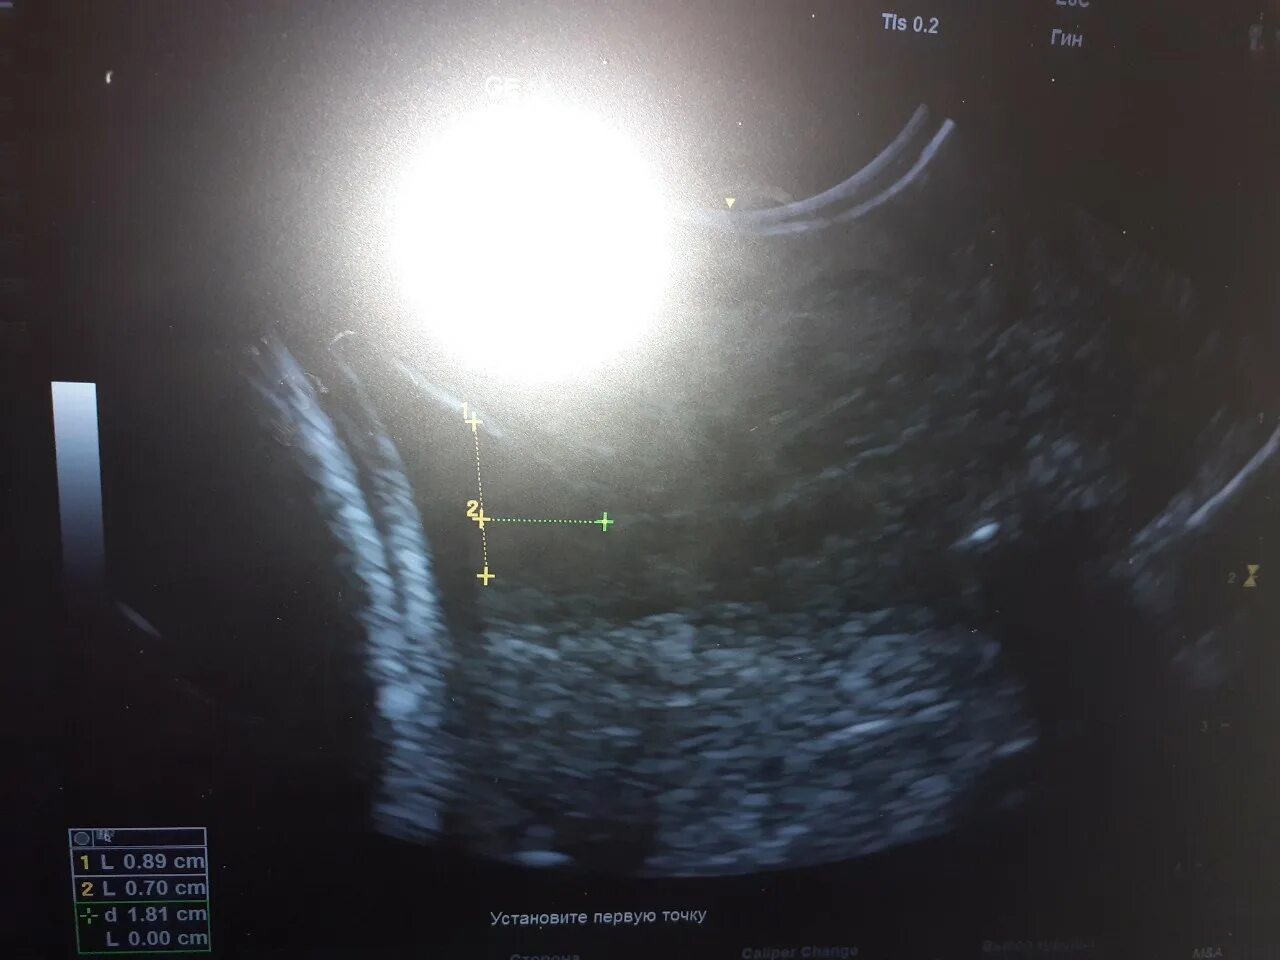

Цервикометрия как делают